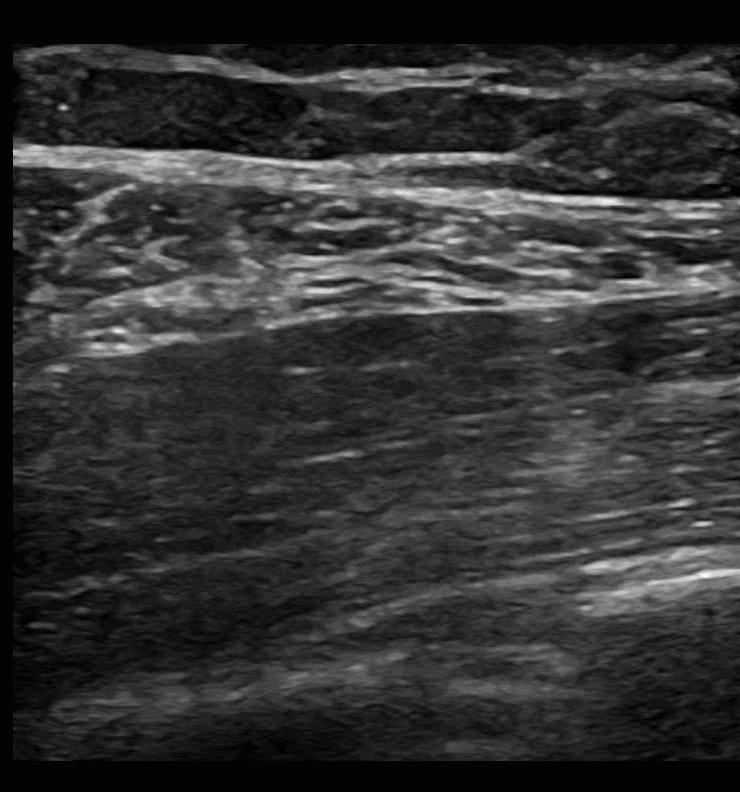

SAPB 1: Pre-scan. The latissimus dorsi muscle comes to a point on the right of the screen as you scan posterior to anterior. Just deep to the latissimus dorsi muscle is the serratus anterior muscle. Deep to the serratus anterior muscle is the rib and pleura.